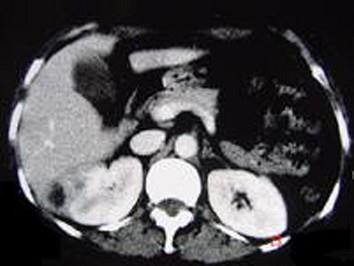

问题 女,12岁,右腰部疼痛10天,尿检可见大量的脓细胞 CT平扫+增强如图所示,应诊断为 ( )

选项 A、右侧肾癌 B、右肾结核 C、右侧感染性肾囊肿 D、右肾转移瘤 E、右肾脓肿

答案 E